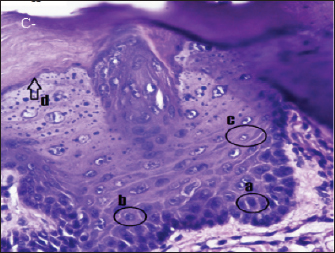

Fig. 2. Histopathologically described the rat tongue epithelium in the negative control group (C-), microscope at ×400. (a) basal layer with a hyperchromatic nucleus and basophilic cytoplasm; (b) spinosum layer with cells of irregular polygonal shape; (c) cells in the granulosum layer with oval cell shape; d. the layer of corneum filled with keratin.

In group (C-), the epithelium of the rat’s tongue had a normal histopathological appearance. There appeared to be a regular epithelial stratification among the cells, with healthy cell turnover in each layer. The base layer consists of hyperchromatic nuclei, while the spinosum layer is composed of irregular polygonal cells. Granulosa has oval-shaped cells. Nucleus and cell organelles vanish, followed by a transition to the corneum layer, demonstrating keratinization development (Fig. 2).

Histopathological examination of the group (C-) revealed no abnormalities in the stratified or basal epithelium. This group did not observe OED because they were not triggered by DMBA. Normal oral epithelium consists of a basal layer of cuboidal or prismatic epithelial cells with hyperchromatic nuclei and basophilic cytoplasm. There are several cells with irregular polygonal shapes in the spinosum layer. The granulosum layer contains oval-shaped cells. The further above granulosum layer, nucleus is lost, and the layer becomes flatter. The outermost layer is the corneum layer, which contains no nucleus and is composed of keratin.